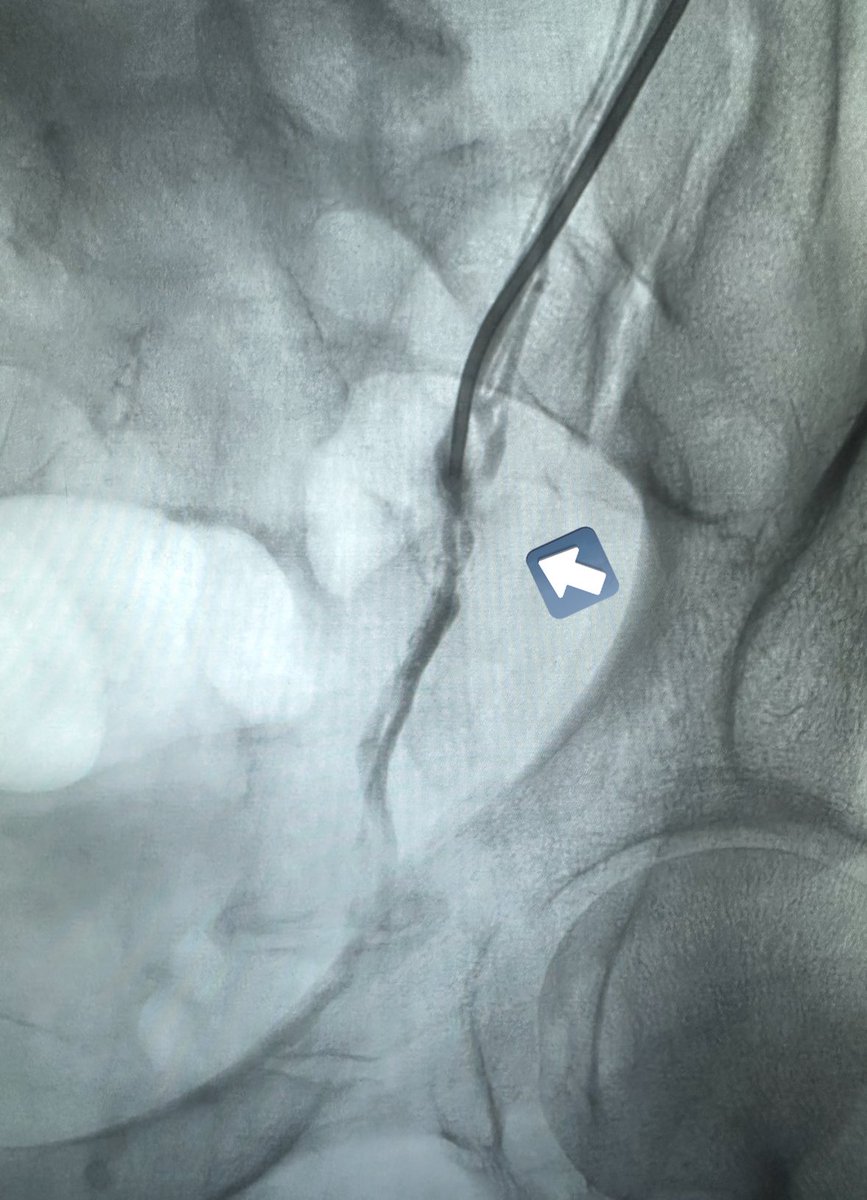

من النوادر أن تكون دوالي الخصية اليمين أكبر من اليسار. بالقسطرة ، يمكن الكشف وعلاج الجهتين بسهولة عن طريق قسطرة واحدة باليد (فتحة لا تتجاوز ٢ مم) ويمكن علاج كل الدوالي حتى الصغيرة. ماذا عن الجراحة؟ يحتاج الجراح لعمل شق جراحي (٢-٣ سم) في كل جهة وفقط يمكنه ربط الدوالي الكبيرة…

طريقة تغلغل الصمغ الطبي في علاج الأوردة المغذية لدوالي الخصية بالقسطرة. اغلاق جميع الأوردة بدون المساس بالقنوات الليمفاوية (فلا يحصل قيلة مائية) ولا الشعيرات الشريانية الدقيقة (فلا يحصل ضمور) القسطرة والأشعة التداخلية اثبتت بالابحاث افضليتها على الجراحة من كل النواحي